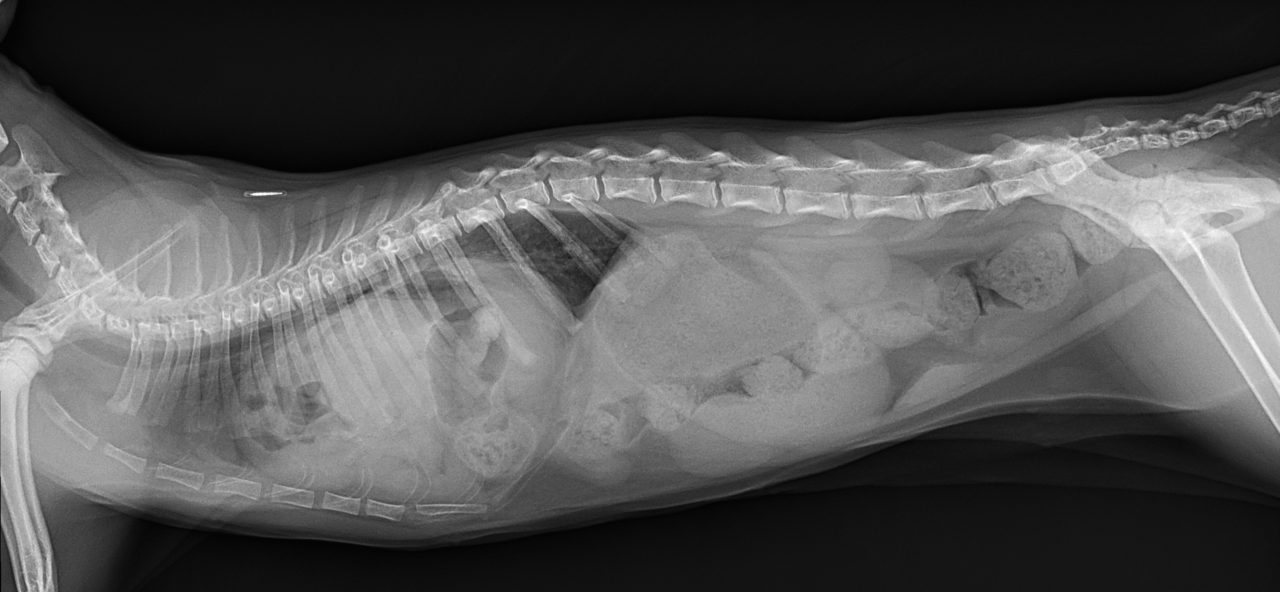

先天性心嚢横隔膜ヘルニア

若い猫が、普段はとても元気だけど、遊んだ後などに咳をする。呼吸が早くなる時がある。などの呼吸器症状で主治医を受診しました。エックス線検査の結果、心嚢横隔膜ヘルニアと診断されました。主治医より、外科的な対応のため紹介受診となりました。腹部正中切開の後、心嚢内に逸脱した、肝臓、胆嚢、小腸を腹腔内に戻し、横隔膜を再建しました。術後には、再拡張性肺水腫という病態が発生する可能性があるため、24時間体制で、患者さんを見守ります。幸い、肺水腫の傾向はみられず、5日目に無事に退院となりました。周術期には一時的に低酸素症に陥ったり、二酸化炭素濃度が上昇したりと、不安定な場面もありましたが、小さな体で本当によく頑張ってくれました。これで、普通の子猫としてどんどん大きく成長してくれると思います。本当によかった。